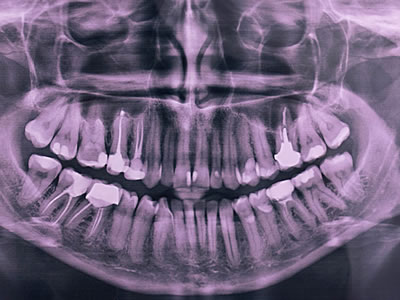

Dental X-rays

They help dentists visualise diseases of teeth and surrounding tissues that cannot be seen with a simple oral exam. They are also helpful for finding and treating dental problems early in their development.